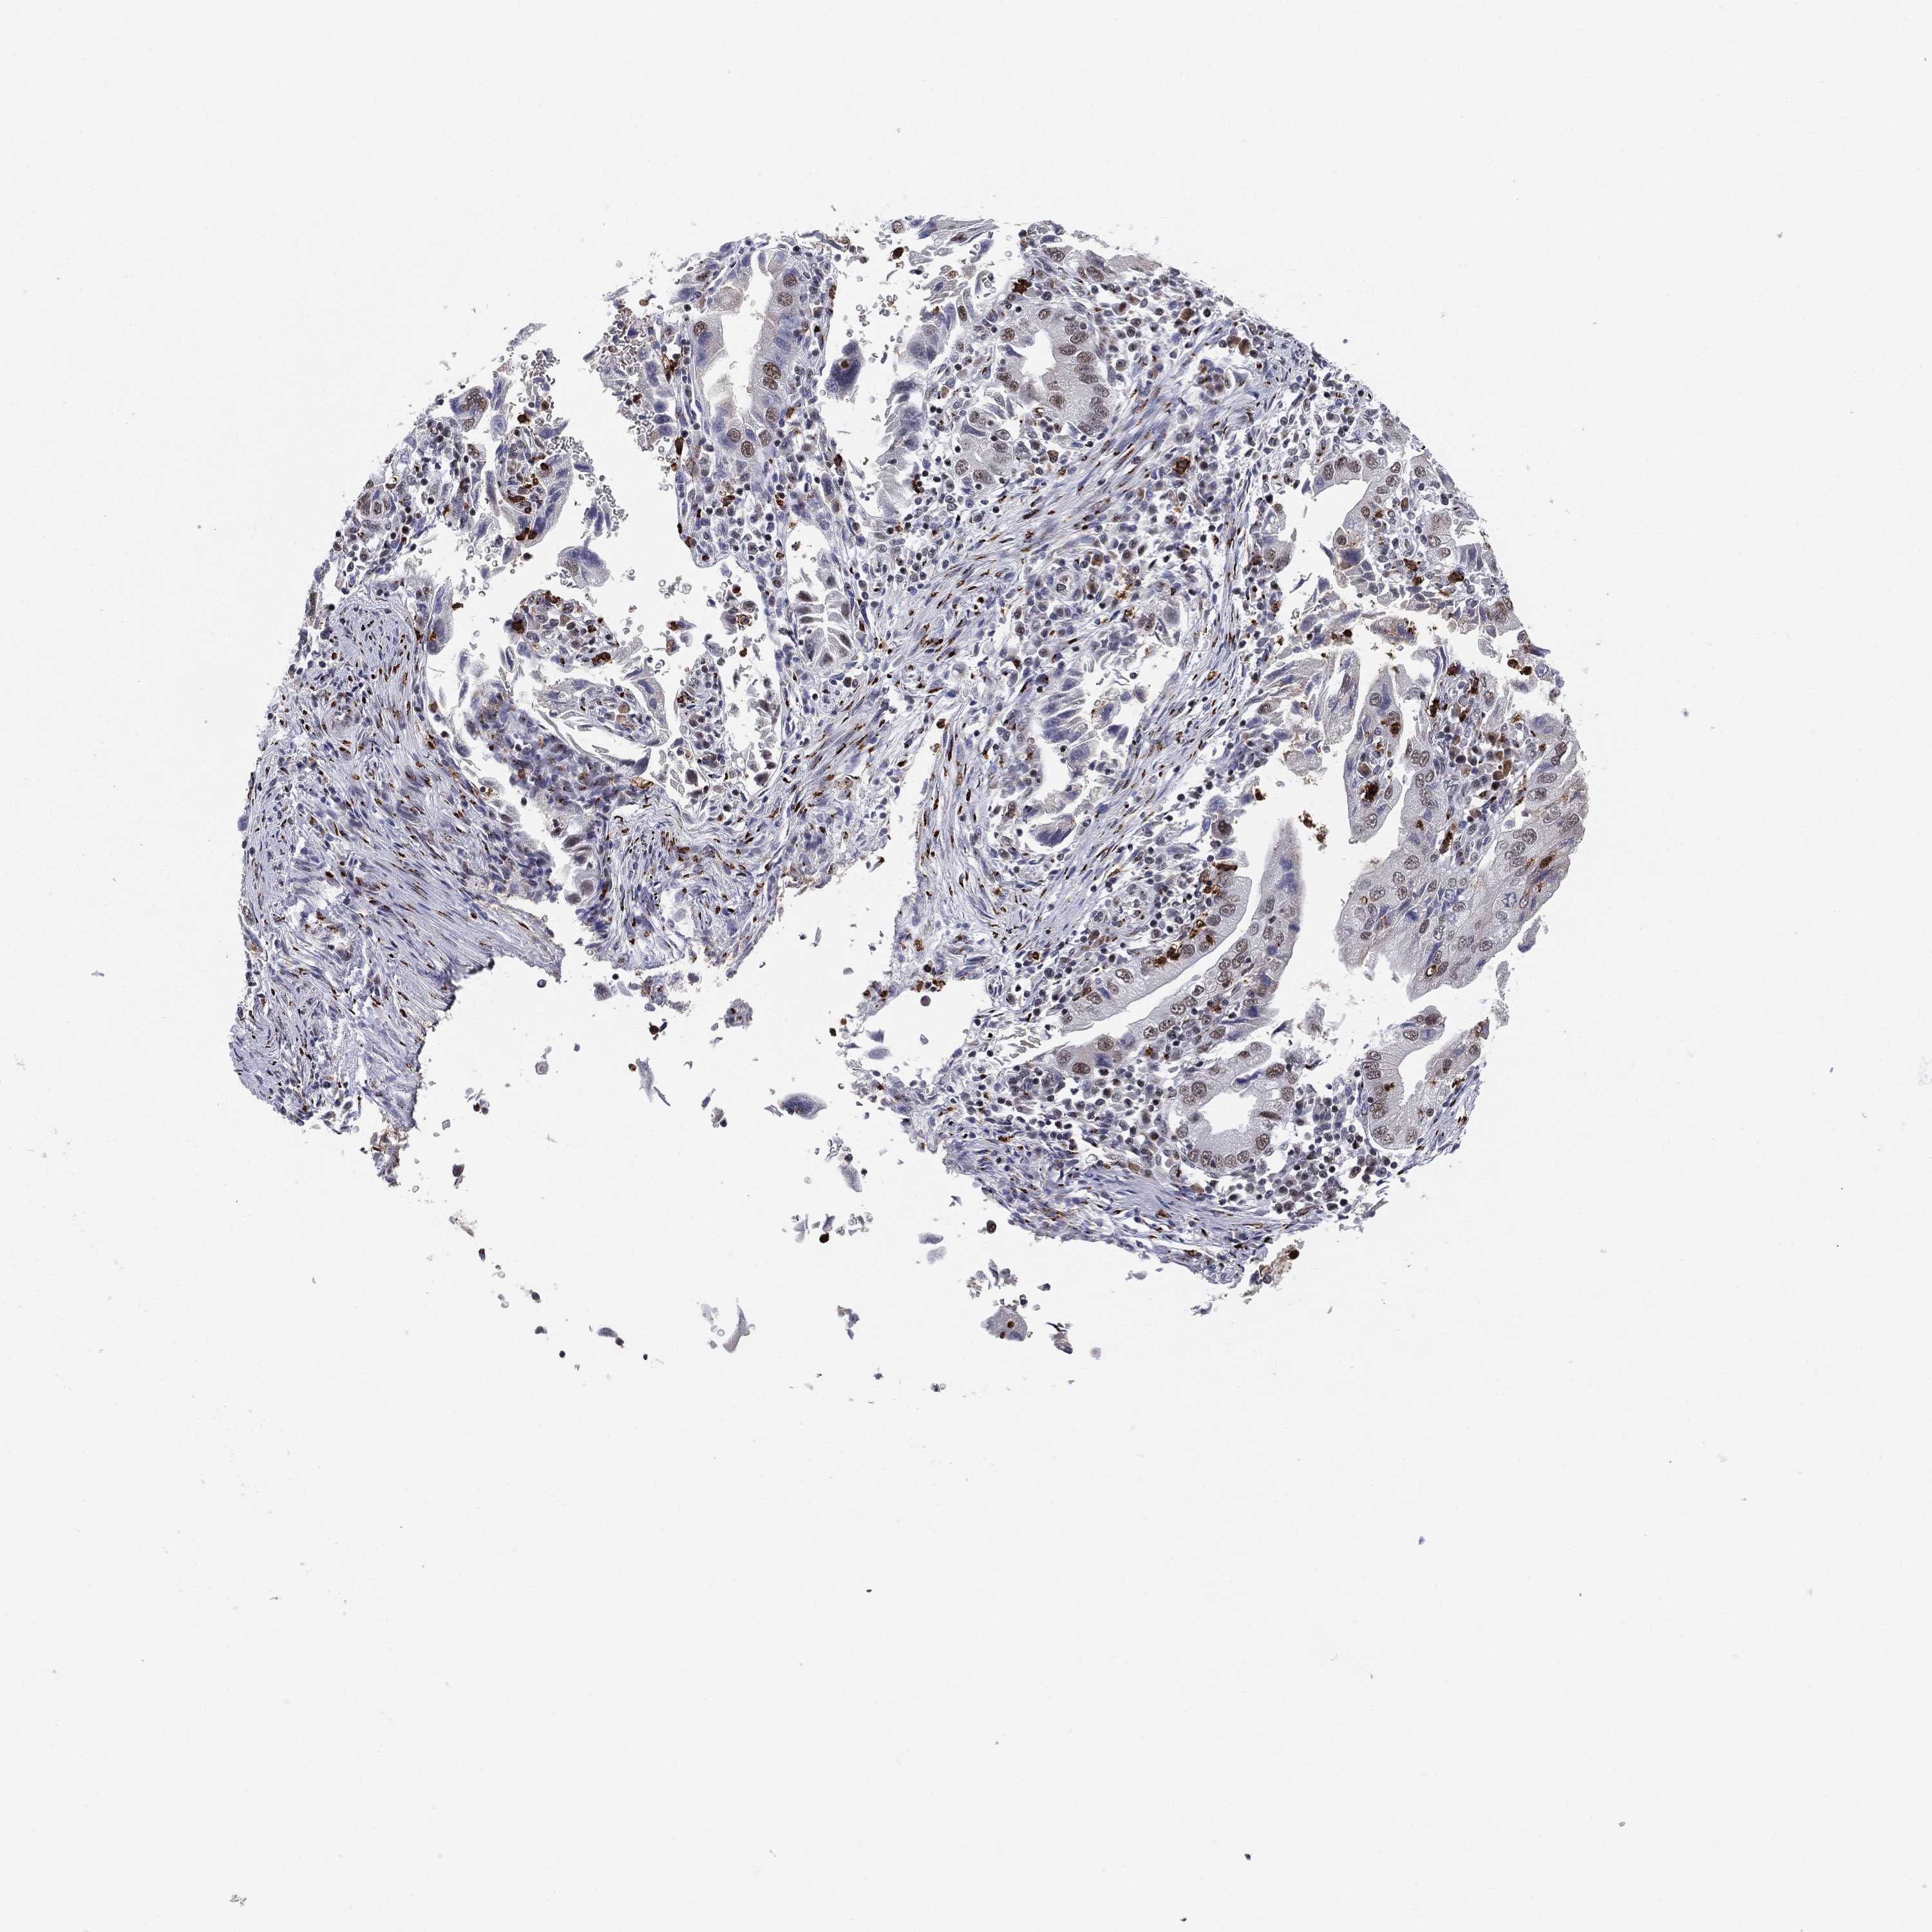

STOMACH CANCER - Protein expressioni

A mouse-over function shows sample information and annotation data. Click on an image to view it in a full screen mode. Samples can be filtered based on level of antibody staining by selecting one or several of the following categories: high, medium, low and not detected. The assay and annotation is described here.

Antibody stainingi

Antibody staining in the annotated cell types in the current human tissue is reported as not detected, low, medium, or high, based on conventional immunohistochemistry profiling in selected tissues. This score is based on the combination of the staining intensity and fraction of stained cells.

Each image is clickable and will lead to virtual microscopy that enables deeper exploration of all samples and also displays staining intensity scores, fraction scores and subcellular localization as well as patient and tissue information for each sample.

Antibody HPA041820

Antibody HPA046601

Antibody HPA077640

Staining

High

Medium

Low

Not detected

Intensity

Strong

Moderate

Weak

Negative

Quantity

>75%

75%-25%

<25%

None

Location

Nuclear

Cytoplasmic/membranous

Cytoplasmic/membranous,nuclear

Adenocarcinoma, NOS

Adenocarcinoma, High grade